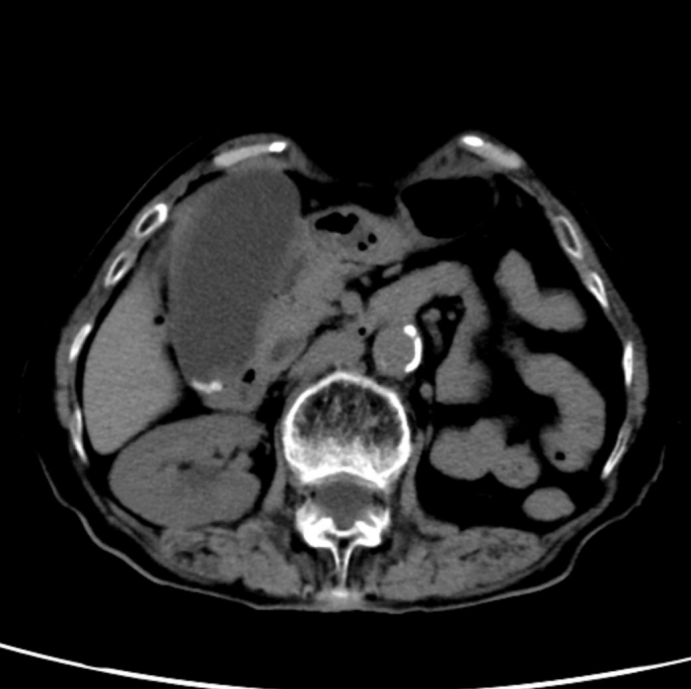

(术后腹壁微创切口图片)

手术台上,罗凤球主任带领团队采用三孔腹腔镜技术,还特意用了低气腹压力操作,最大程度减少对张婆婆呼吸和循环系统的影响。凭借着精湛的技术和丰富的经验,整个手术只用了20分钟就成功切除了胆囊,术中出血量还不到1毫升,创伤特别小。

罗凤球主任术后解释说:“给高龄老人做手术,不光要把病治好,还要尽量减少手术对身体的伤害。低气腹压力和精细操作能减少对内脏的刺激,帮助老人术后更快恢复。”